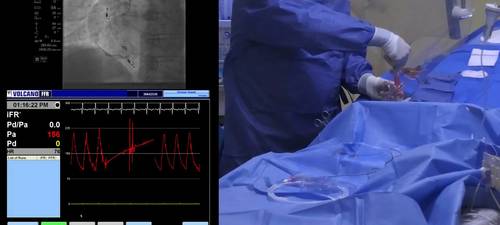

Justin Davies takes through the rationale behind the administration of intracoronary nitrates prior to physiological assessment, and the technique for giving the medication.

• Rationale for administration of intracoronary nitrates

• Dosing

• Timing prior to measurement